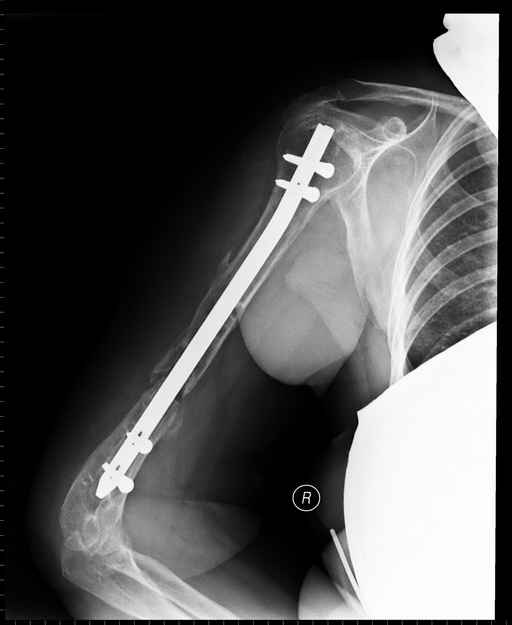

Больная 48 лет, медсестра-массажист, перелом плеча 7 лет назад, оперирована 4-кратно и безуспешно

Больная 48 лет, медсестра. Травма получена 7 лет назад, оперирована первично в Турции - остеосинтез пластиной - несращение - реостеосинтез стержнем там же через год (обычным, с выстоянеием его в полость плеча) - несращение - поступила к нам впервые в марте 2008 года - удаление стержня, реостеосинтез пластиной и костная пластика, в течение 2 лет лизис кости вокруг винтов, смещение фиксатора, в марте 2010 - удаление пластины, реостеосинтез интрамедуллярным стержнем с блокированием (рассверливание + костная пластика). В динамике - вновь лизис в области перелома, нестабильность дистальных блокирующих винтов.

Клинически фиксация пока действительно стабильна, но на рентгенограммах резорбция кости в области дистальных блокирующих винтов и миграция одного из них.